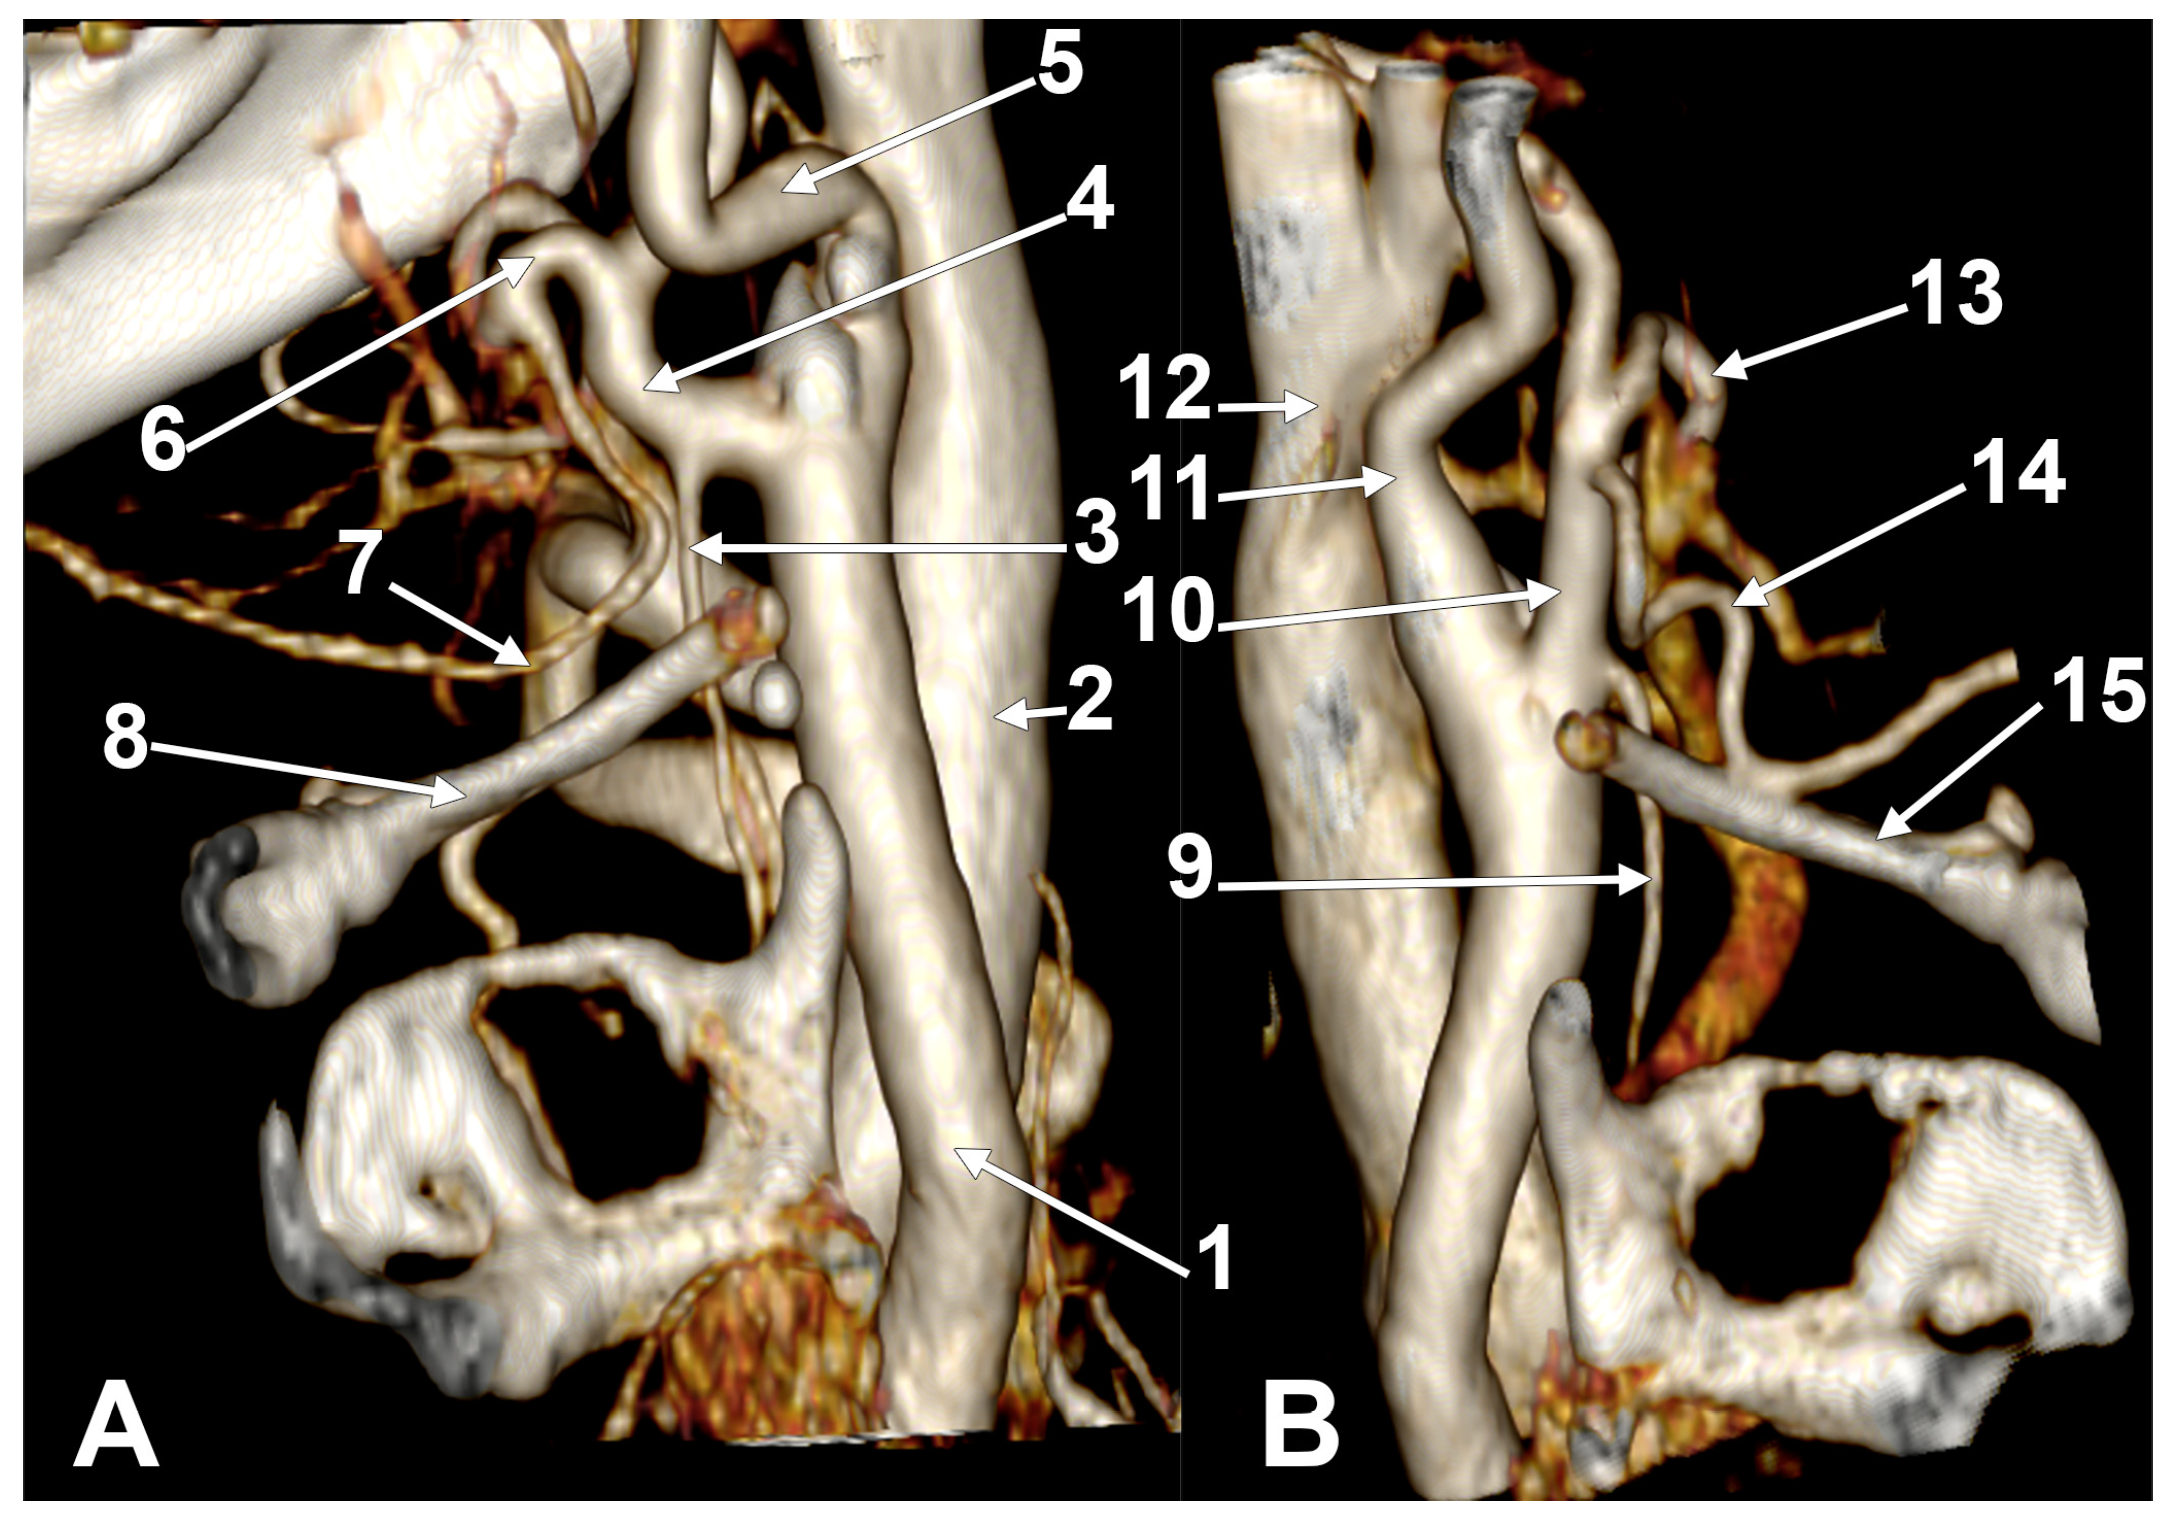

Appendix A.2. Supplemental Figures